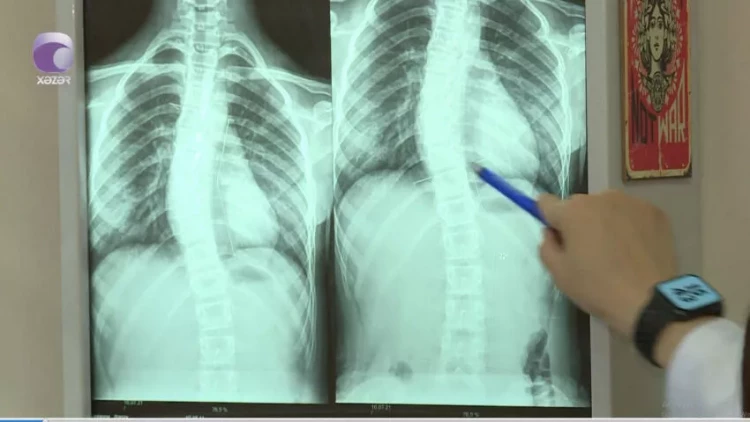

"Son zamanlar 8-12 yaş aralığındakı uşaqlarda bel və boyun ağrıları ilə bağlı şikayətlər nəzərəçarpacaq dərəcədə artıb.

Halbuki, illər öncə uşaqlarda belə problemlər olmurdu. Bunu fizioterapevt Səidə Kərimova "Xəzər xəbər"ə müsahibəsində deyib.

meqale.com xəbər verir ki, həkim səbəb olaraq bildirdi ki, uşaqların çantaları kifayət qədər ağırdır. Çiyin ağrıları isə xüsusən ona görə yaranır ki, ağır çantaları daşıyarkən, kəmərləri uşağın yumşaq toxumasını sıxıb kəsir.

Həkim bildirdi ki, bu yaşda uşaqlar oturanda, xüsusilə də dərs oxuyarkən, qamətini dik tutmalıdır.